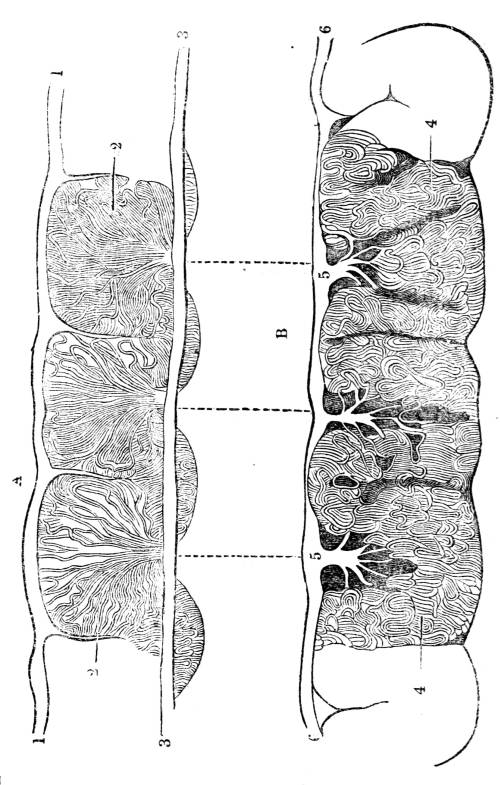

Fig. CXXXIV.—

View of the Respiratory Apparatus in

Man.

1. The Trachea. 2. The right lung. 3. The left lung.

4. Fissures, dividing each lung into, 5. Large portions

termed lobes. 6. Smaller divisions termed lobules. 7.

Pericardium. 8. Heart. 9. Aorta. 10. Diaphragm separating

the cavity of the thorax from that of the abdomen.

357. In man there are two pulmonary bags (fig.

CXXXIV. 2, 3), of nearly equal size, which, together

with the heart, completely fill the large cavity

of the thorax (fig. CXXXIV.), their external surface

being everywhere in immediate contact with

the thoracic walls. One of these bags is placed on

the right side of the body, constituting the right

lung (fig. CXXXIV. 2), and the other on the left,

constituting the left lung (fig. CXXXIV. 3). Each

lung is divided by deep fissures, into large portions

called lobes (figs. CXXXIV. 4, and CXXXV.

6), of which there are three belonging to the

right, and two to the left lung. Each lobe is

subdivided into innumerable smaller parts termed

lobules (figs. CXXXIV. 6, and CXXXV. 6), while the

lobules successively diminish in size until they

terminate in minute vesicles that constitute the

great bulk of the organ (fig. CXXXV. 8).

Fig. CXXXV.—

View of the Air Tubes and Lung.

1. The larynx. 2. Trachea. 3. Right bronchus. 4.

Left bronchus. 5. Left lung; the fissures denoted by the

two lines which meet at 6, dividing it into three lobes,

and the smaller lines on its surface marking the division of

the lobes into lobules. 7. Large bronchial tubes. 8. Minute

bronchial tubes terminating in the air cells or vesicles.

1. The trachea. 2. The right and left bronchus; the left

bronchus showing its division into smaller and smaller

branches in the lung, and the ultimate termination of the

branches in the air vesicles. 3. Right auricle of the heart.

4. Left auricle. 5. Right ventricle. 6. The aorta arising from

the left ventricle, the left ventricle being in this diagram

concealed by the right. 7. Pulmonary artery arising from

the right ventricle and dividing into, 8. The right, and

9. The left branch. The latter is seen dividing into smaller

and smaller branches, and ultimately terminating on the

air vesicles. 10. Branches of one of the pulmonary veins

proceeding from the terminations of the pulmonary artery

on the air vesicles, where together they form the net-work

of vessels termed the Rete Mirabile. 11. Trunk of the

vein on its way to the left auricle of the heart. 12.

Superior vena cava. 13. Inferior vena cava. 14. Air vesicles

magnified. 15. Blood-vessels distributed upon them.